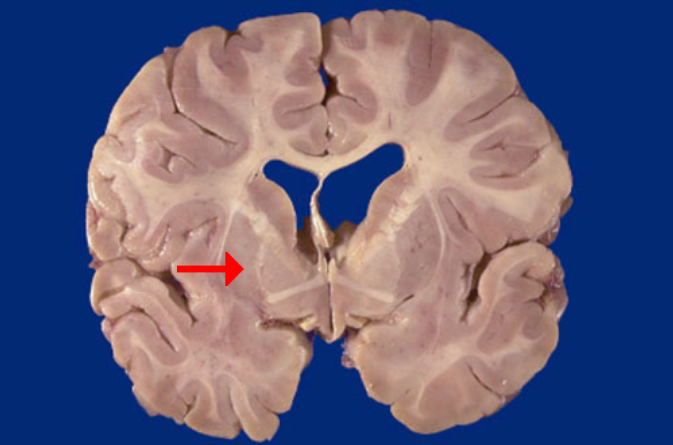

Label this brain structure

Putamen